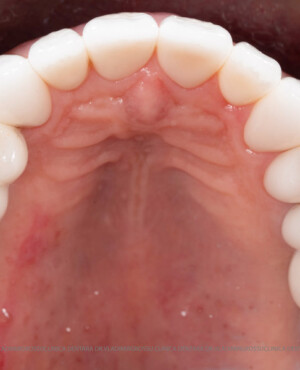

Adiția osoasă are un rol crucial pentru poziționarea corectă și stabilă a implanturilor dentare. Clinica stomatologică Dr. Grossu din Chișinău promovează o abordare chirurgicală estetică și predictibilă, adaptată fiecărui caz în parte.

Medicii noștri au o vastă experiență atât în chirurgia estetică, cât și în protezarea cu un grad înalt de naturalitate, ceea ce ne permite să gestionăm cu succes și cele mai complexe cazuri.